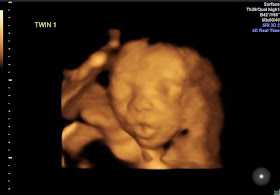

So, after all that explaining our disappointment (well, not disappointment so much as feeling underwhelmed), here are our pictures! We were pretty lucky with baby boy being in a great position allowing them to get some good views.

They went back to baby boy to get some more views of him and we saw him yawning and pouting big time!

| Don't worry, he doesn't have a hole in the side of his face, he'd just moved out of the plane of the scan for the 3D program to work properly |

| A pout to rival Anna! |